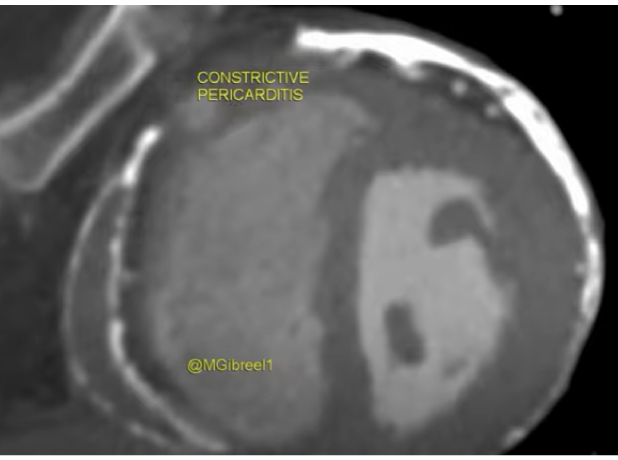

CONSTRICTIVE PERICARDITIS

Mohamed Gibreel

, FEBR (Fellowship of Egyptian Board of Radiology ) Cardiac imaging consultant at Aswan heart center -Magdi Yacoub Foundation , Egypt

cardiac CT

CT